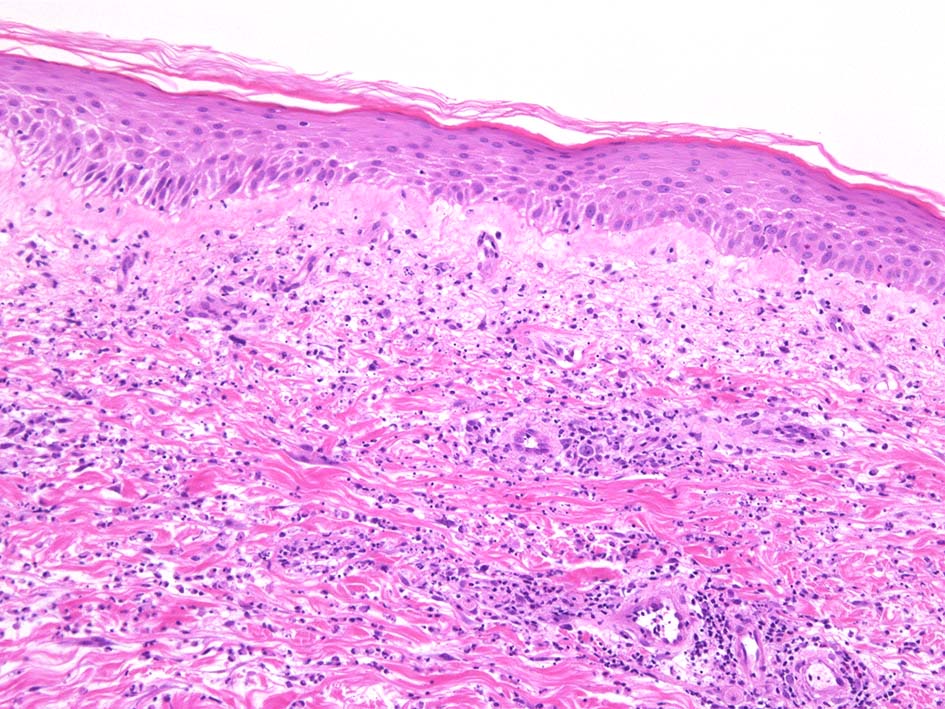

典型疹は真皮の好中球浸潤より始まる. 病初期では, 好中球浸潤は表皮に及ばない. 病期が進むにつれ, 2次的好中球浸潤が認められるようになる.

真皮上中層で広範囲に好中球が密に浸潤する所見がSweet病の最大の特徴. 好中球活性が亢進し, apoptosisを起こして核塵(核破砕物)がみられることが多い. 浸潤が顕著になると真皮上中層が浮腫をきたして, 皮疹が隆起する.

真皮上層浮腫がつよくなり表皮下水疱を形成することがある. 水疱内にはフィブリンや炎症細胞が多数認められる.

真皮の好中球浸潤部には毛細血管, 細動静脈が巻き込まれるが, 血管のフィブリノイド壊死は認められない.(鑑別が難しいことのあるBehçet病では2012年より, 壊死性血管炎があるとされており鑑別のための病理所見となっている)

表皮基底層の液状変性, また液状変性ほど強くなくともvesicleの形成が見られることがある.

HE x40. Sweet病最盛期皮膚病変の所見があります.

表皮下水疱, 真皮上層の細血管周囲に密な好中球浸潤あり.(thumb nail clickで大きなphotoが見られます)